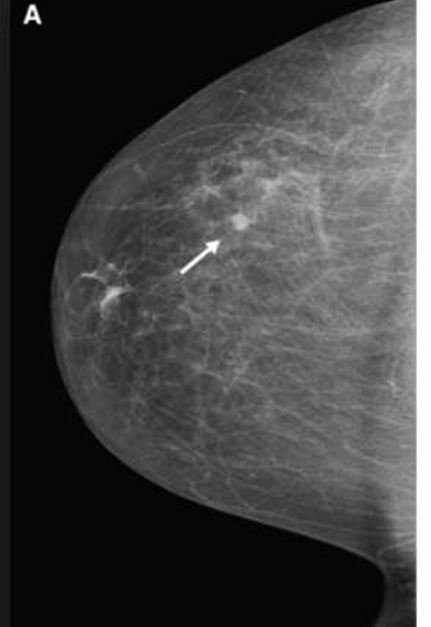

round well defeined

irrigular shape mass

speculated margin

–MICROCALCIFICATION

The typical high-risk finding will be a speculated mass with abnormal architecture & asymmetry, with clustered micro- calcification

breast cancer means:

irregular margin

speculated mass